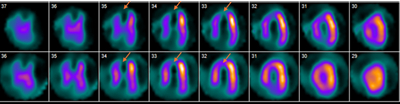

A 60-year-old male with no prior medical history presented with lightheadedness and stable exertional chest pain. Vital signs and physical examination were unremarkable. Electrocardiogram showed normal sinus rhythm with an old inferior and anteroseptal infarction. Echocardiography revealed normal EF with no clear wall motion abnormalities. A myocardial perfusion stress test showed moderate fixed reduced radiotracer uptake with mild reversibility at the LAD territory (Figure 1). Coronary computed tomography angiography revealed a calcified and non-calcified plaque in the proximal to mid LAD with apical LVT (Figure 2[A-B]). Left heart catheterization showed a total mid LAD occlusion with collateral circulation from the acute marginal branch of the right coronary artery to distal LAD (Figure 3[A-B]). Further work-up revealed a JAK2 V617F mutation. The patient was treated with apixaban, atorvastatin, and metoprolol.